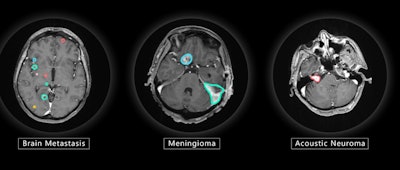

VBrain maps three types of brain tumors -- metastasis, meningioma, and acoustic neuroma -- allowing patients to begin radiation therapy more quickly than when contouring must be performed manually, the company said.